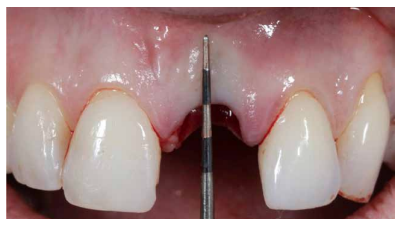

Conclusiones: La rehabilitación sobre implantes en situaciones de pérdida dental en el sector anterior estético y en especial, en pacientes jóvenes, requiere un plan de tratamiento multidisciplinar en cuanto a la extracción del diente y colocación del IOI en la posición tridimensional correcta, existiendo diferentes aspectos a tener en cuenta para ello, especialmente el remanente óseo residual, la posición del margen gingival, así como la preservación y acondicionamiento de los tejidos duros y blandos periimplantarios mediante injertos y un manejo correcto de una prótesis provisional hasta conseguir un perfil de emergencia y contorno gingival ideal antes de la corona definitiva

Conclusions: Rehabilitation on implants in situations of tooth loss in the aesthetic anterior sector, especially in young patients, requires a multidisciplinary treatment plan in relation to tooth extraction and placement of the OII in the correct three-dimensional position. There are various aspects to be taken into account, particularly the residual remaining bone, the position of the gingival margin, as well as the preservation and conditioning of the peri-implant hard and soft tissues by means of grafts and proper handling of a provisional prosthesis until an ideal emergence profile and gingival contour is achieved before the final crown.

Los beneficios de la carga inmediata incluyen una reducción notable de las intervenciones quirúrgicas, una menor dilatación temporal del tratamiento e incluso un mejor bienestar psicológico y social para el paciente. En casos con importante compromiso estético, la carga inmediata o la provisionalización inmediata, añadida a la colocación inmediata postextracción del IOI permiten minimizar las alteraciones derivadas de la pérdida dental, manteniendo el perfil de emergencia, contorno de tejidos blandos y las papilas gingivales5-7.

Así mismo, se han establecido diferentes protocolos para el manejo del sector estético anterosuperior, que se suman al acto de la colocación inmediata del implante y la corona provisional, donde se incluyen la colocación de un material no reabsorbible entre el IOI y la cortical vestibular para minimizar el posible colapso, así como el manejo de los tejidos blandos periimplantarios8-11.